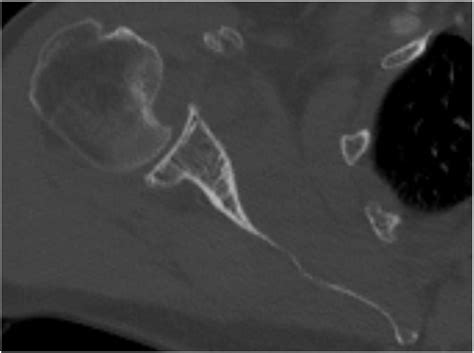

The shoulder is a ball-and-socket joint, designed for a vast range of motion. However, this flexibility comes at the cost of stability. When an anterior shoulder dislocation occurs, the humeral head is pushed forward and out of the socket. In many cases, the bone travels until it strikes the glenoid rim. Because the bone of the humeral head is relatively soft, the harder bone of the glenoid rim acts like a stamp, creating a “divot” or notch in the humeral head.

This indentation is the Hills Sachs lesion. It is important to note that these lesions are highly prevalent in patients who experience recurrent shoulder instability. Once the bone has been dented, the "locking" mechanism of the shoulder is compromised, making it easier for the joint to dislocate again in the future. This creates a cycle of instability that often requires medical intervention to correct.

CT Scan The gold standard for quantifying the amount of bone loss in the humeral head and glenoid.